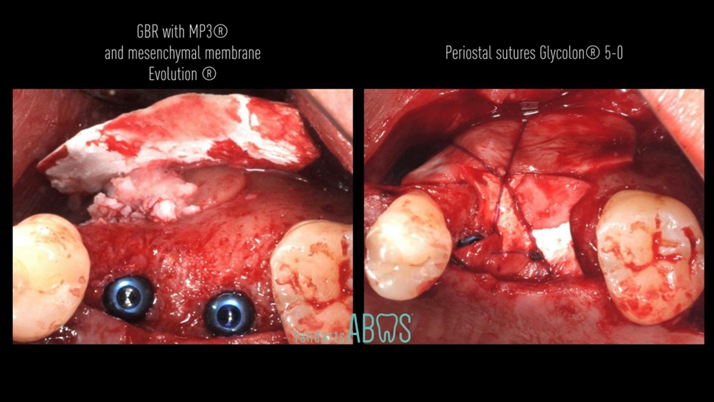

Clinical case: Installation of dental implants in complicated anatomic conditions using crest lifting methods

- Courtesy of Dr.Alexander Lysov, Russia -

Keywords

AnyRidge, complicated anatomic conditions, crest lift, MICA Kit, Dr. Alexander Lysov, bone regeneration, GBR, #26, maxillary posterior

Products:

AnyRidge implant system, MICA Kit